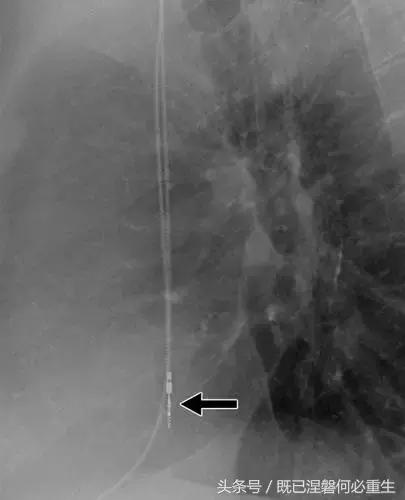

图。 7A 79岁的男性患有电极折断和迁移。

A,初始胸前X线片显示Pacesetter双腔起搏器低于锁骨的心房导线不完全断裂(变薄)(箭头)。

图。 7B 79岁的男性患有电极折断和迁移。

B,大约3年后,电极完全断裂,金属传导碎片(箭头)分离。 远端片段(箭头)已经偏移尾侧,但是由于围绕电极的射线可穿透鞘的约束效应而没有迁移到肺循环中。 引线和中心静脉导管最常见于锁骨和第一肋骨之间断裂,因为它们在臂运动期间被锁骨下肌肉或腱或肋锁韧带压缩[16]。

造成设备故障的最常见的X光检查原因之一是铅断裂。锁骨下静脉经过锁骨下的部位是骨折最常见的位置[16](图7A和7B)。在这个位置的损伤可能发生在导管或导线,并已被描述为锁骨下夹断综合征和锁骨下压溃综合征[16?18]。临床上,骨折的导线通常在患者中产生可以是连续的,间歇的或依赖于患者定位的症状。识别这些状况可能需要挑衅性的动作,例如等长臂锻炼,仰卧或侧向定位或Valsalva。设备检查将显示异常的起搏阻抗(如果绝缘破裂允许导体暴露则减小,如果导体断裂但绝缘完好则增加),感测错误和起搏捕获损失[12]。导线断裂或绝缘损坏可能导致感测或起搏异常。对心律失常的不适当的过感知或欠感应可能导致不适当的治疗,例如抗心动过速起搏和休克治疗,或不适当的抑制治疗。